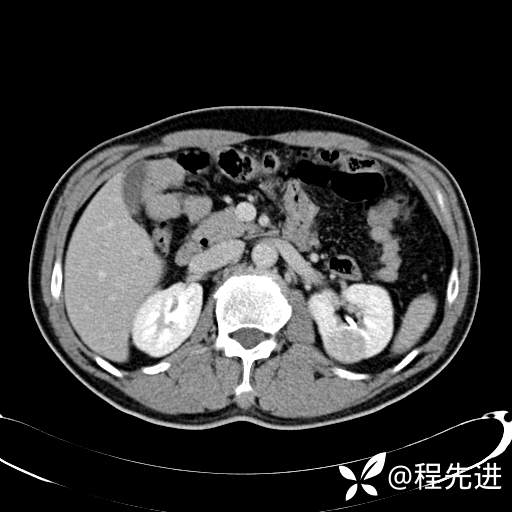

患者性别:男

患者年龄:65岁

简要病史:腰痛2月,体检发现左肾占位5天

平扫: